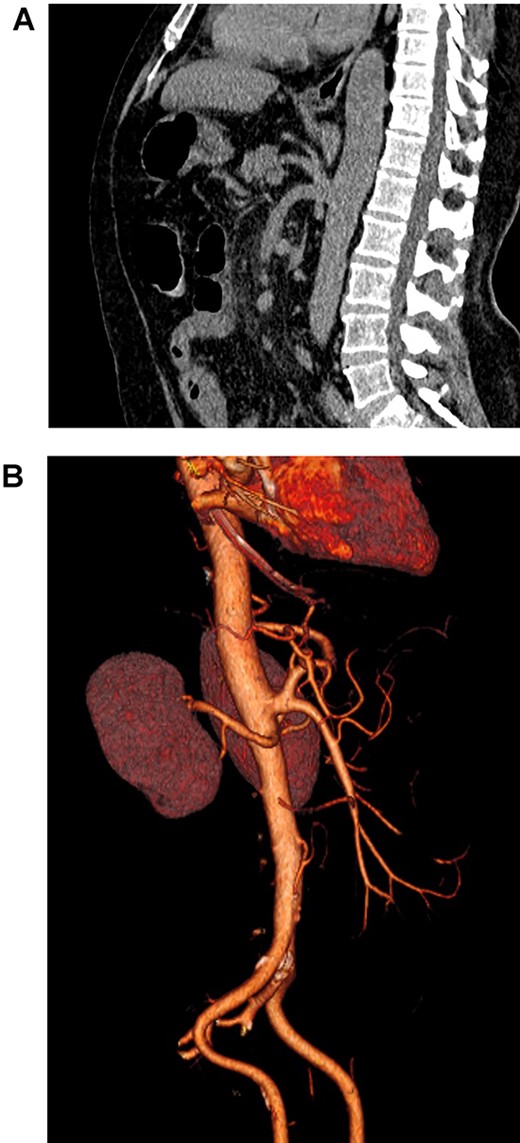

On the CT, the whole extent of the bowel was dilated; however, no free liquid, air or masses were found (Fig. 1). Nevertheless, the patient’s abdominal pain and distention worsened. Due to this, surgical consultation was needed, and after obtaining consent, surgery was decided as intestinal ischemia was among the differential diagnosis.

(A). Abdominal CT, showing the celiacomesenteric trunk. (B). Abdominal 3D reconstruction, revealing the vascular variation.